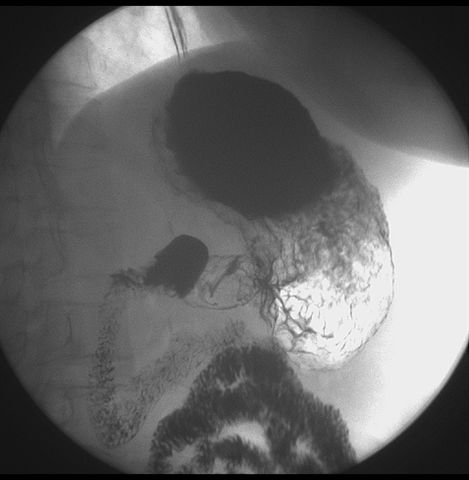

标题: X6872:F,69y,胃部不适。

胃窦至幽门段胃壁僵硬,扩张受限,局部纠集粘破坏,呈杵状。提示溃疡癌变可能性大。

胃窦癌可能性大,建议胃镜活检。钡剂太稀,吃的有点多。

支持考虑胃窦癌可能,胃内滞留液太多,胃窦部僵硬。

瀑布型胃,胃粘膜那是一个乱,窦部充盈不好,第16幅窦部粘膜反倒又很顺,先定个胃炎胃窦炎胃窦癌待排之类,建议进一步作胃镜检查。

胃窦部见钡池影,局部粘膜紊乱,纠集呈杵状改变,胃壁扩张受限,胃窦癌可能性大,建议胃镜检查.

胃窦部管腔扩张度较差,形态略有改变,胃窦粘膜显示欠佳,胃窦部占位可能性大,结合胃镜活检。

北京肿瘤医院胃镜诊断皮革胃。